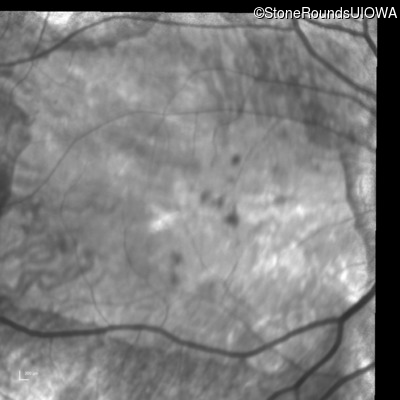

Infrared Fundus Photograph - Right - 20/250 sc

Exemplar